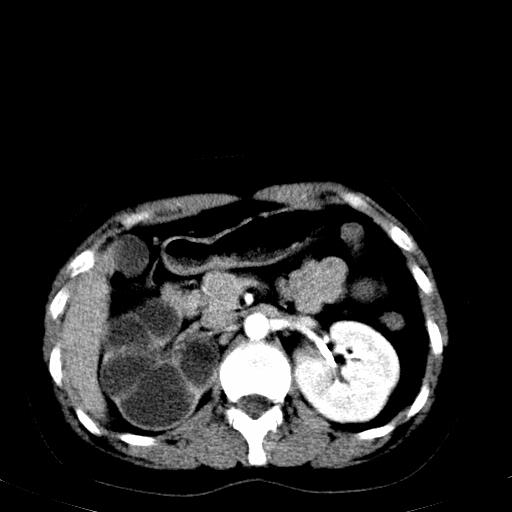

患者体检发现右肾体积增大,怀疑右肾积水

右肾重度积水,以肾盏积水明显,有分隔,上段输尿管轻度扩张,管壁增厚,考虑肾结核可能,请结合尿检查,胸部拍片排除肺结核。

右肾重度积水,建议ct向下扫描或逆行造影,左肾及左输尿管结石 .

左肾不像是结石吧,是不是做过造影啊

第一个序列应该是延迟图像吧;

结合强化图片看ivp意义不大,建议作逆行造影看一下;

左肾不是结石,是造影后改变.右肾积水,功能仅存.